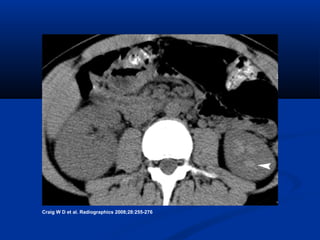

Noncontrast



Normal

Nephromegaly

 Perinephric stranding

 Loss of hyperdense pyramids

 Hyperdensities (hemorrhage)

 Thickening of urothelium

 Mild ureteral dilation

• #14 Figure 7.  Acute bacterial pyelonephritis. (7) Unenhanced CT scan from a clinically documented case of acute bacterial pyelonephritis shows asymmetric enlargement and absence of the pyramids of the right kidney (cf the preserved pyramids [arrow] in the normal left kidney). Loss of the renal pyramids is a nonspecific marker for edema, which is more typically seen in obstruction related to calculi.